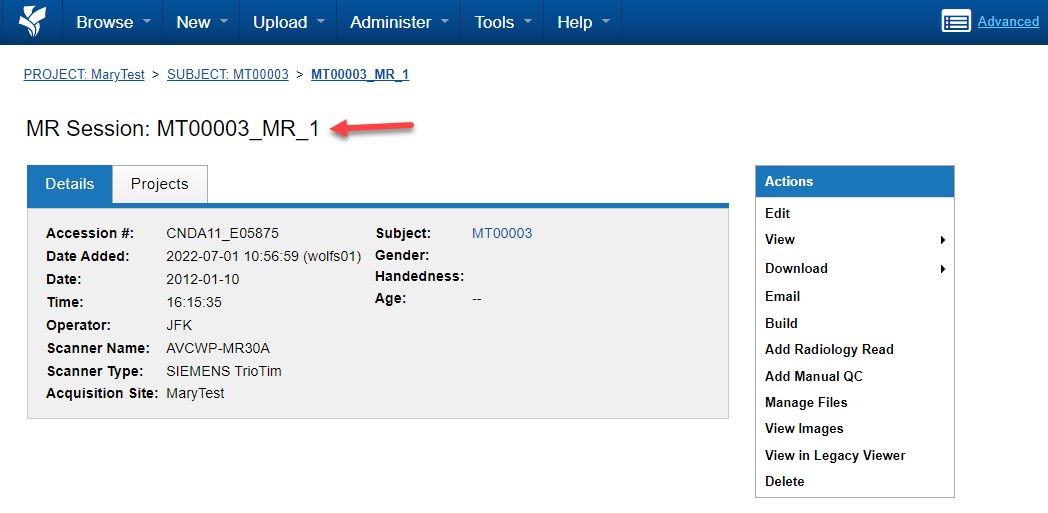

Verifying Upload in CNDA

After upload completes:

- Log in to CNDA.

- Navigate to your project.

- Select the subject.

- Open the session.

Confirm:

- All expected series are present

- Total file counts are correct